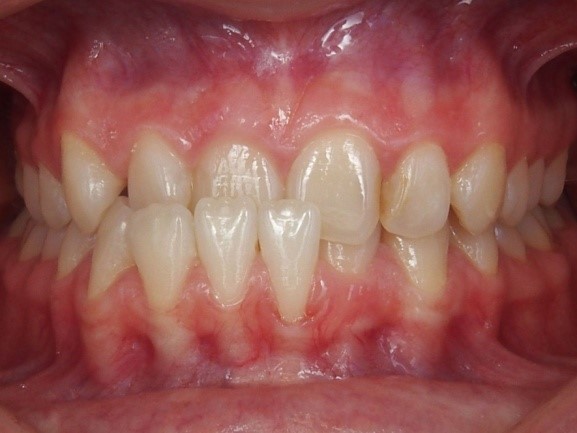

4. Crowding

De tanden staan gedraaid en scheef over elkaar door ruimtegebrek. De tanden zijn hierbij te groot, de kaken te klein of het betreft een combinatie van beide.

Bij crowding is het lastig om de tanden goed schoon te houden waardoor er makkelijker gaatjes en tandvleesproblemen kunnen ontstaan. Ook kan er sneller aanslag en tandsteen blijven zitten. Verder is het esthetisch minder fraai.